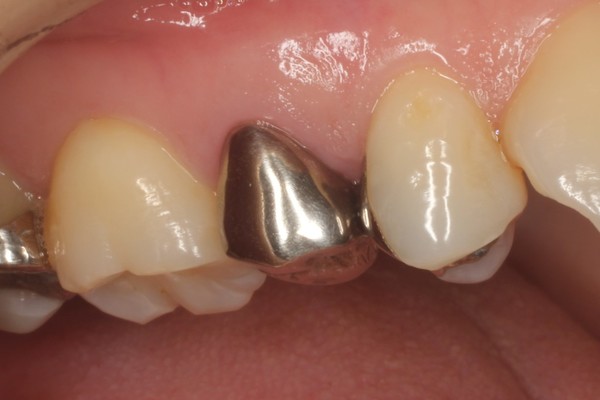

治療写真 術前 パラジウムインレー(銀歯)。10年以上が経過し劣化している。 術後 適合精度の高い(ぴったりと合った)クラウンおよびインレーが装着された。色調も調和している。 パラジウムクラウンを除去し仮歯に置き換えた。5,9 Posts See Instagram photos and videos from '銀歯' hashtag30代女性 銀歯をダイレクトボンディングで白く治療した症例 ご相談内容 笑ったときに銀歯が見えるのが気になっていたそうです。 歯を白くしたい、永く保つようにしたいとのことでご相談くださいました。 診断結果 ご相談のとおり、下の奥歯が銀歯で